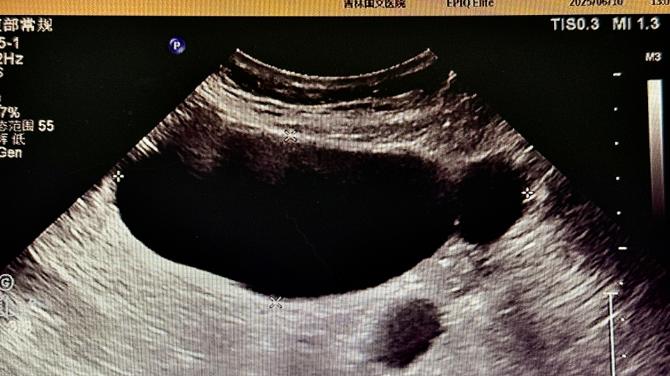

精准超声揪出肠道“隐形杀手”——国文超声科联合多学科确诊一例复杂结肠肿瘤